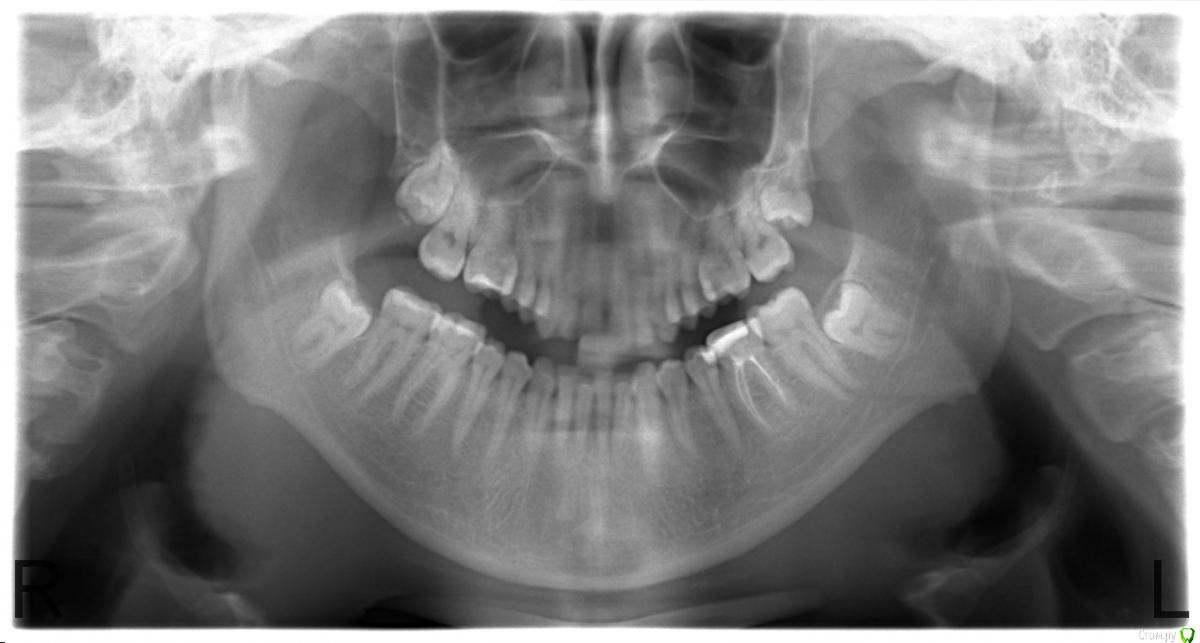

Katerina2019 Опубликовано 4 апреля, 2019 Поделиться Опубликовано 4 апреля, 2019 Здравствуйте !Побывала в двух клиниках с жалобой на частую (раз в 3-4 месяца) ноющую боль в области нижних зубов мудрости. В одной мне сказали, что удалить все 4 зуба мудрости можно относительно легко, и "только после этого можно будет поставить каппы/брекеты, т.к. сейчас из-за зубов мудрости остальные зубы сдвинуты друг к другу а после удаления 8-ок могут поменять свое положение". Во второй - что с одной стороны (слева на снимке) это очнеь трудно, а с другой стороны (справа на снимке) это невозможно, цитирую: "зубы сидят глубоко, и хирург может задеть челюстной нерв в нижней челюсти, т.к. неясно где точно он проходит. в результате чего могут быть проблемы с мимикой в дальнейшем. рекомендуем оставить все как есть. вам уже 30 лет, зубы мудрости не будут расти раз до исх пор ни один не показался из десны". Нижние зубы продолжают иногда ныть, в области 7 зуба(слева на снимке)дважды ставилась пломба, сейчас чувствую им холодное и кислое, но в двух клиниках сказали что не видят там под пломбой кариеса, только "кариозное пятно". Планирую на днях сделать КТ для полной картины, но пока решила написать сюда т.к. есть панорамный снимок. Ссылка на комментарий